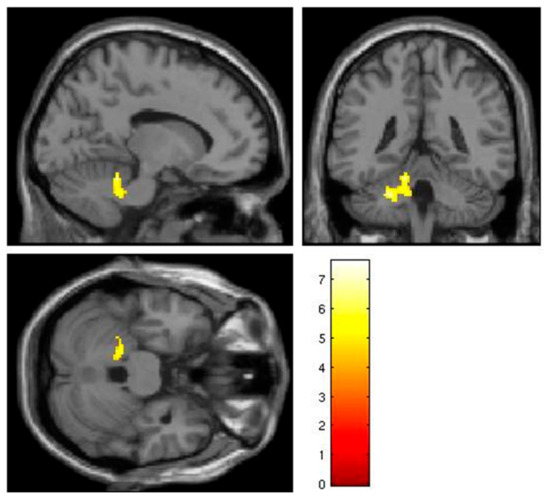

| Left cerebellum, anterior lobe, lobules IV/V | 0.029 | 198 | 4.01 | −24 | −42 | −34 |

| Left cerebellum, anterior lobe, lobules IV/V | 0.006 | 27 | 3.70 | −20 | −38 | −30 |